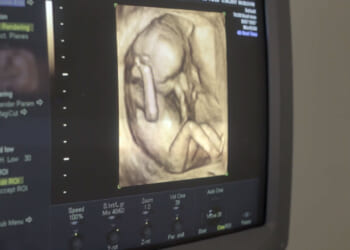

In Kentucky, One Attorney General Takes on the Abortion Pill Pipeline – PJ Media